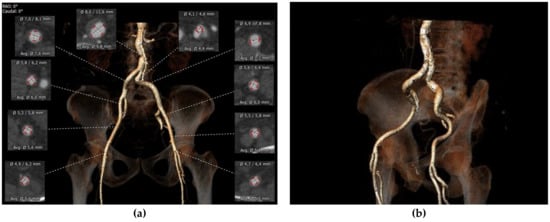

2.3.1. Peripheral Access

Femoral access is the preferred access for TAVI. MDCT imaging identifies patients with complex vasculature anatomies, which may impact the decision to use an alternative vascular approach (i.e., transapical, transaxillary, or direct aortic) [31]. Vessel size and diameters, degree of calcification, vessel tortuosity, and high-risk features can be properly identified by CT through multiple projections (Figure 2a,b).

Figure 2.

(a) Preoperative measurements of peripheral accesses for TAVI feasibility. (b) Preoperative femoral and iliac courses evaluation.

In a prospective study of 130 patients undergoing TAVI, Hayashida et al. found that vascular complications and 30-day mortality were associated with a sheath-to-femoral artery ratio (SFAR) of 1.05 or higher [32]. Later, Okuyama et al. proposed a change in this cut-off value, believing that this was too strict, providing high sensitivity but poor specificity, and 1.12 may be more appropriate (Table 1) [33].

Interestingly, the most recent valve delivery systems have a size ranging between 14 and 20 Fr, depending on the specific prosthesis valve type and size. While some years ago, a minimal lumen of femoral arteries of 6.0–6.5 mm was required, currently, with reduced delivery profiles, TAVI might also be indicated in patients with peripheral vessels as small as 5.0 mm [34].